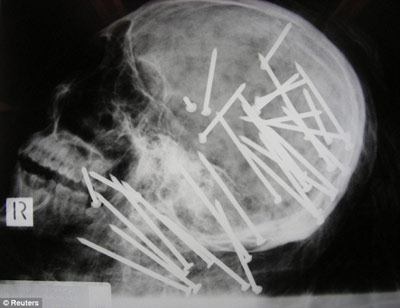

X光顯示,劉晨(音譯)頭部和頸部被釘有30枚鋼釘

據(jù)報道,該男子名叫劉晨(音譯),于2000年移民澳大利亞墨爾本市,4年后搬往悉尼。2008年11月,劉晨的男性友人向悉尼警方報案,稱其已經(jīng)失蹤一段時間,警方遂展開調(diào)查。兩周后,兩名在悉尼喬治河上劃船的男孩發(fā)現(xiàn)了劉晨已經(jīng)高度腐爛的浮尸。警方稱,當時劉晨被一條毯子緊裹著,四肢被電線捆得結(jié)結(jié)實實,警方將尸體交與法醫(yī)進行X光檢查后驚異地在他頭部和頸部發(fā)現(xiàn)了30枚鋼釘。

負責本案的警官馬克·紐漢表示:“尸檢結(jié)果顯示,兇手用一種無繩氣動式射釘槍對著死者的頭部和頸部開了30槍,這種標準式射釘槍哪都可以買到?!毕つ峋窘芊颉へ惱姿垢5赂嬖V記者:“這起謀殺案令所有的警察震驚不已,在我36年的辦案生涯中,還從來沒見過性質(zhì)如此惡劣的兇案……就是因為這起謀殺案是如此的殘忍,所以我們希望公眾能夠為警方提供更多的破案線索?!?/p>